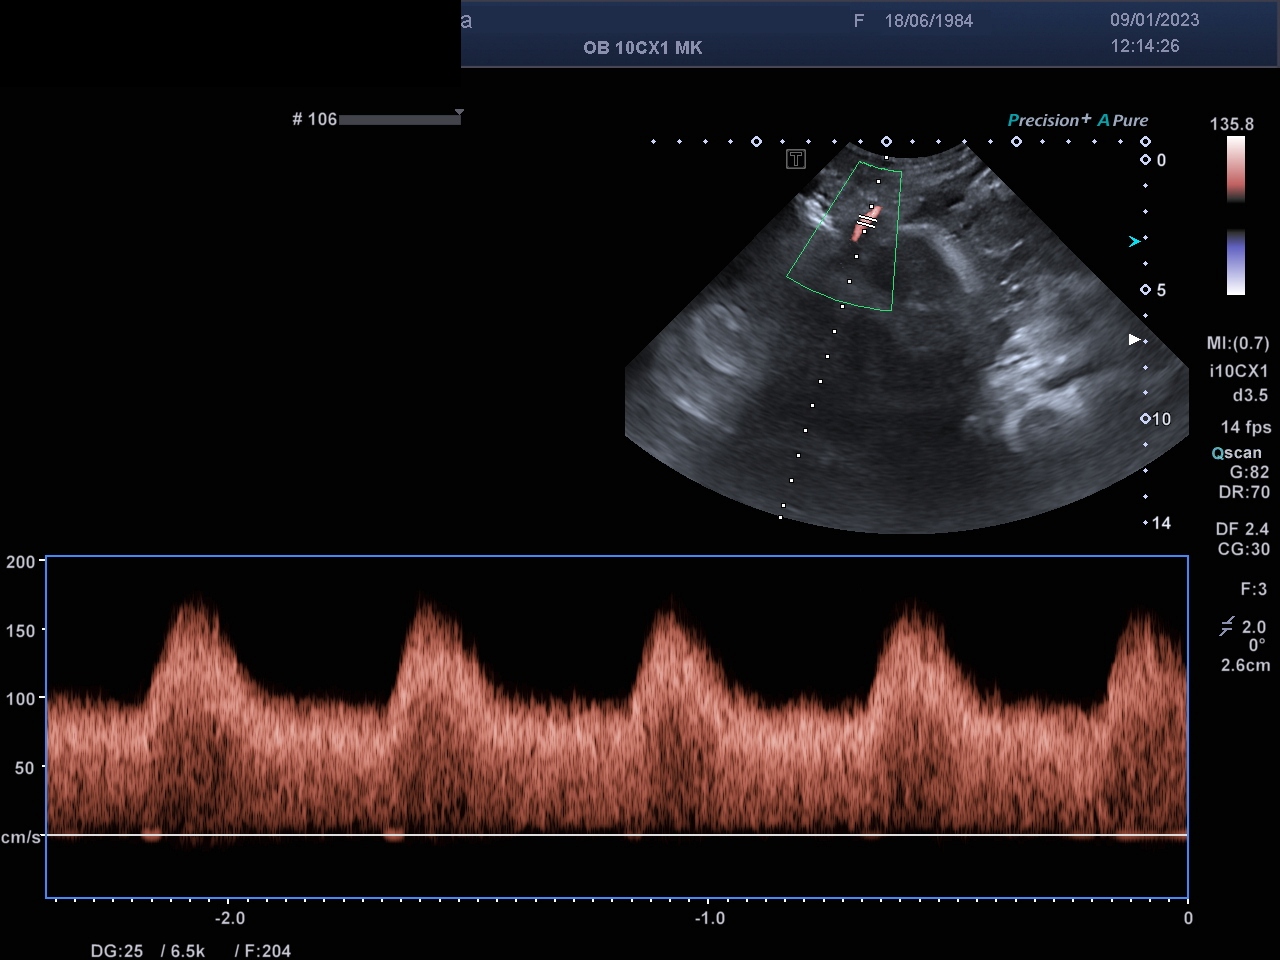

Farb-/ und Spektraldopplersonographie

Mit der Farbdopplersonographie können fetale und mütterliche Gefäße dargestellt werden und dann Spektraldopplerkurven erstellt werden, die semiquantitativ mittels Indices auswertet werden . Damit ist eine Zustandsbeurteilung des Feten als auch der Durchblutungsverhältnisse der Gebärmutterarterien der Schwangeren möglich.

Die Farb-/ und Spektraldopplersonographie ermöglicht die Zustandsbeurteilung des Feten.